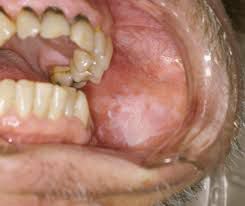

What is leukoplakia

Leukoplakia is a condition in which one or more white patches or spots (lesions) forms inside the mouth. Leukoplakia is different from other causes of white patches such as thrush or lichen planus because it can eventually develop into oral cancer.